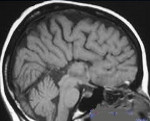

Q04.4 Септооптическая дисплазия